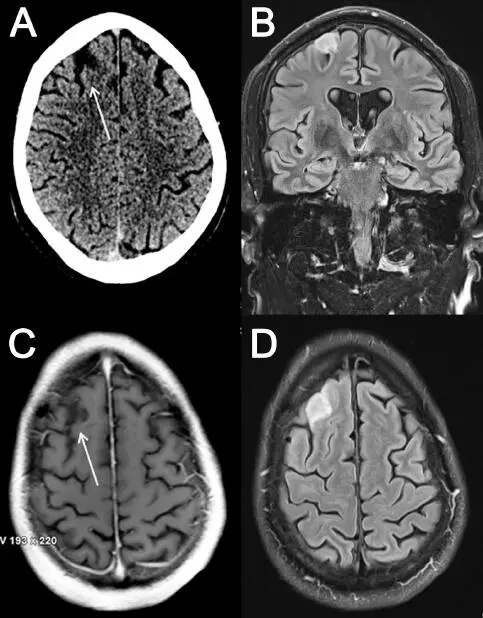

Ein 57-jähriger Vertriebsleiter erlitt einen erstmaligen unprovozierten tonisch-klonischen Anfall von ca. drei Minuten Dauer ohne beobachteten oder erinnerten fokalen Beginn. Es dauerte 20 Minuten, bevor der Patient kognitiv wiederhergestellt war. Während das postiktuale EEG frei von epilepsietypischer Aktivität war, zeigten die cerebrale Computertomografie (cCT) und die Magnetresonanztomografie (MRT) eine rechts frontal kortikale Läsion, die kein Kontrastmittel aufnahm. Die neuroradiologische Diagnose lautete »Rindenastrozytom« (

Abb. 1.1 Abb. 1.1: (A) axiale Computertomogramm; der Tumor im rechten Frontallappen ist mit einem Pfeil markiert; (B) koronare Magnetresonanztomografie (MRT), Sequenz: Fluid-attenuated inversion recovery (FLAIR); (C) axiale T1-gewichtete MRT mit Kontrastmittel (der Tumor nimmt kein Kontrastmittel auf); (D) axiale FLAIR-MRT

Abb. 1.1: (A) axiale Computertomogramm; der Tumor im rechten Frontallappen ist mit einem Pfeil markiert; (B) koronare Magnetresonanztomografie (MRT), Sequenz: Fluid-attenuated inversion recovery (FLAIR); (C) axiale T1-gewichtete MRT mit Kontrastmittel (der Tumor nimmt kein Kontrastmittel auf); (D) axiale FLAIR-MRT